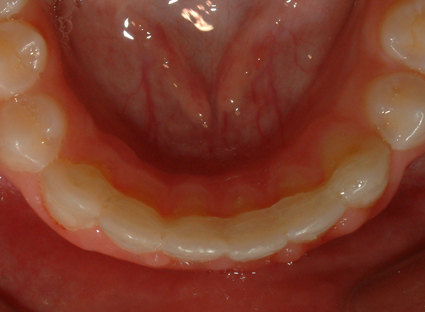

Απεικονίζονται οι διάφοροι κινητοί και ακίνητοι μηχανισμοί συγκράτησης του αποτελέσματος της ορθοδοντικής θεραπείας

Μετά από την ολοκλήρωση της ενεργού φάσης της ορθοδοντικής θεραπείας, πάντοτε διατηρείται κάποια (διαφορετική για κάθε περίπτωση) πιθανότητα για υποτροπή της θεραπευμένης ορθοδοντικής ανωμαλίας. Οι ιστοί του στόματος και ειδικότερα εκείνοι που εντοπίζονται γύρω από τα δόντια, σε γενικές γραμμές διαθέτουν ισχυρή μνήμη και μέσω αυτής, επιδιώκουν συνεχώς την επαναφορά των δοντιών στην αρχική τους θέση, ακόμη και μετά την ολοκλήρωση της ορθοδοντικής θεραπείας. Για το λόγο αυτό, η ορθοδοντική θεραπεία δεν πρέπει να θεωρείται ότι ολοκληρώθηκε μετά την αφαίρεση των ορθοδοντικών μηχανισμών. Ο ασθενής από την πλευρά του, πρέπει να κατανοήσει την ιδιαίτερη σημασία που έχει η φάση της συγκρατήσεως του θεραπευτικού αποτελέσματος, κατά την οποία πρέπει να ακολουθεί πιστά τις οδηγίες του ορθοδοντικού του, ώστε το αποτέλεσμα της θεραπείας να είναι σταθερό. Ως ένας αδρός κανόνας, ισχύει ότι, όσο μεγαλύτερη και βαρύτερη είναι η αρχική ορθοδοντική ανωμαλία, τόσο μεγαλύτερο διάστημα θα απαιτηθεί να διαρκέσει η συγκράτηση του θεραπευτικού αποτελέσματος. Με τα κατάλληλα κατά περίπτωση συγκρατητικά μέσα, τα δόντια διατηρούνται παθητικά στις νέες τους θέσεις, στις οποίες έχουν μετακινηθεί με την ορθοδοντική, για το απαραίτητο χρονικό διάστημα, ώστε να αποκτήσουν "νέα μνήμη" και να σταθεροποιηθούν στις θέσεις αυτές. Για τον ίδιο λόγο, μετά την ορθοδοντική θεραπεία, πρέπει πάντοτε να αξιολογείται η φάση διαπλάσεως και η διεύθυνση ανατολής (δηλαδή της εμφάνισής τους στο στόμα) των φρονιμιτών (ή σωφρονιστήρων). Αν και δεν έχει αποδειχθεί, εν τούτοις υποστηρίζεται από ορισμένους ερευνητές, ότι οι φρονιμίτες, προκειμένου να αποκτήσουν τον απαραίτητο χώρο στις οπίσθιες περιοχές του στόματος, μπορούν να ωθήσουν τα πρόσθια δόντια προς τα εμπρός, με την ενδογενή δύναμη που διαθέτουν και έτσι να προκαλέσουν εκ νέου συνωστισμό (δευτερογενώς) των προσθίων δοντιών. Έτσι, τις περισσότερες φορές όπου ο διαθέσιμος χώρος δεν κρίνεται αρκετός για την ανατολή των φρονιμιτών, τότε δίνεται από τον ορθοδοντικό, η εντολή για άμεση εξαγωγή τους ακόμα και σε πρώιμη φάση διάπλασής τους, και μάλιστα πριν εμφανισθούν στο στόμα.